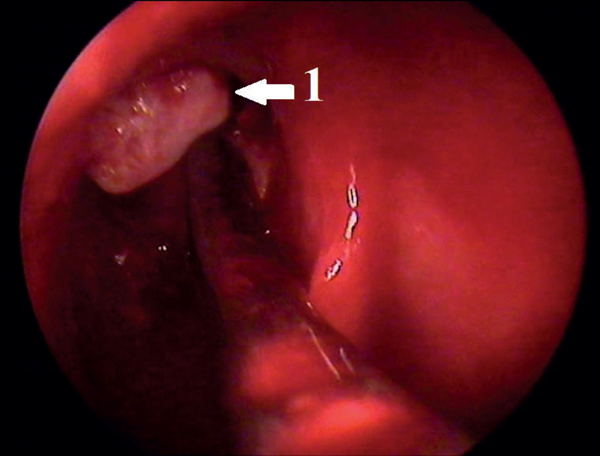

Figure 2: Endoscopic view: 1 - mobilised frontal osteoma.

She was informed beforehand that in case of failure of the endoscopic surgery the tumour would be removed by an open coronal approach. In January 2013 the osteoma was removed under general anaesthesia and controlled hypotension with endoscopic control using a 3D electromagnetic navigation system via endonasal approach. After the tumour was mobilised into the sinus cavity (Figure 2), reduction of its size was necessary to release it from the sinus. Mobilised osteoma was reduced by diode laser applied in contact mode (power 10 W) (Figure 3) and then removed through the nasal cavity (Figure 4). Vaporisation of mobilised bone tumour was held around its circumference with exposure time of 8-10 seconds. When it reached a sufficient size for removing through the expanded frontonasal ostiae, it was extracted by an aspirator. Histological examination showed a mixed osteoma, containing dense and mature bones, fibrous tissue and collagen fibres (Figure 5). A right eyelid oedema was in the early postoperative period. This situation was not accompanied by damage of the optic nerve and violations of the mobility of the eyeball. Systemic antibiotic therapy, glucocorticoids and diuretics were initiated immediately and eyelid oedema passed off within two days. The control CT scan on the third day after surgery showed complete removal of tumours (Figure 6). The patient was transferred to out-patient treatment on the seventh day after surgery. We recommended the use of topical steroids and ENT and ophthalmology dynamic observation.